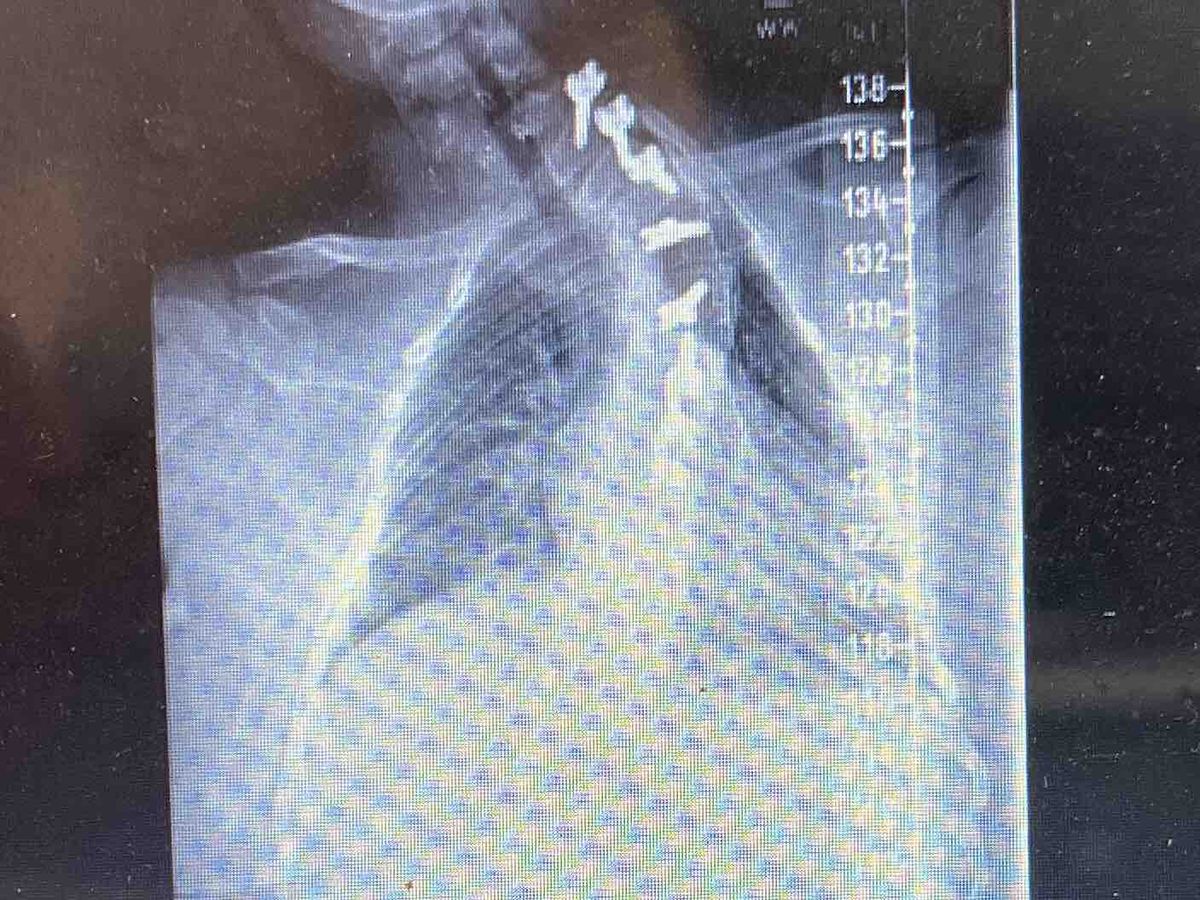

In 2019, Irish was diagnosed with a very aggressive Ideopathic Scoliosis. At that time, the surgeon informed Jennifer and Irish that because the curve in his spine is located up high { where the vertebrae are very small}, he would not be able to straighten his spine in surgery, but could fuse it in place, preventing it from getting any worse, OR, they could try a newer, less invasive surgery called Vertebral Spinal Tethering. They would secure one side of his spine with screws and put a Tethering device on the opposite side. As he grew, the tether would slowly pull his spine into place. They chose the less invasive procedure with the more hopeful outcome. It would be a waiting game. Jen and Irish were patient. Although they never saw improvement and Irish's pain increased, they were encouraged by doctors to "wait and see".

Last week, they were devastated to learn that the Tethering attempt had indeed failed and that Irish must now  have the more invasive Spinal Fusion to stop the progression.  It is now an urgent need as Irish's spine is rapidly getting worse, threatening his lungs and other internal organs. Surgery is scheduled for March 29th.